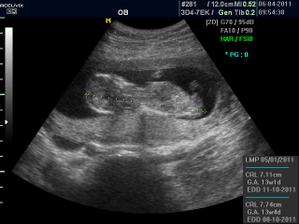

Pidižva č.2 a č.3... :o)